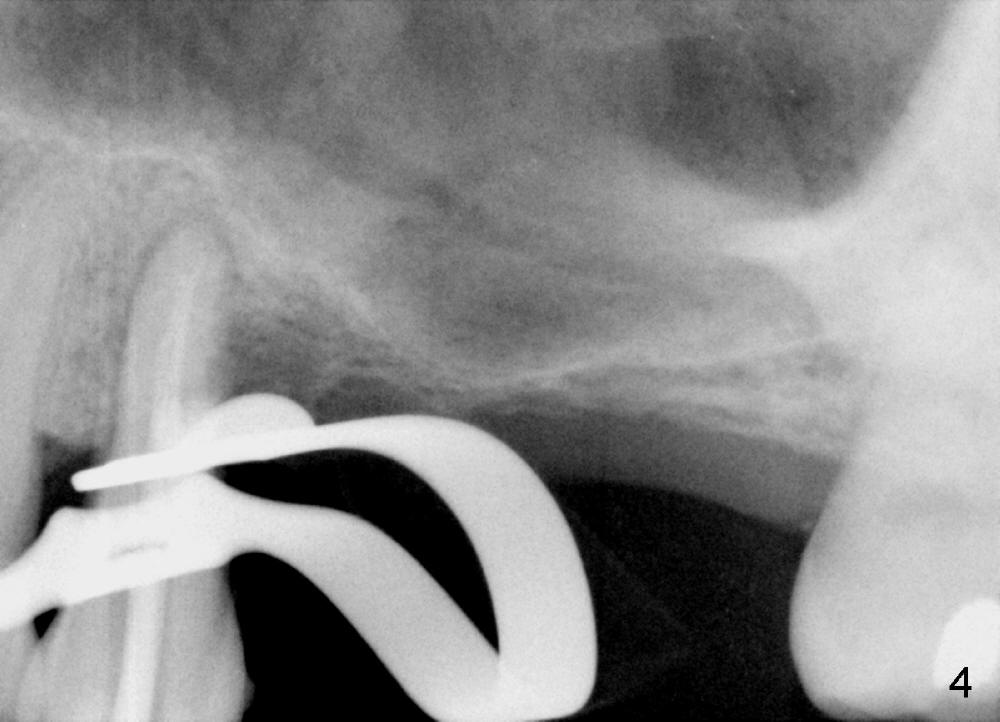

A 44-year-old man has severe periodontitis. The tooth #13 has a distal cervical carious lesion with spontaneous pain (Fig.1 (CT sagittal section) *). The caries is continuous with the buccal canal (Fig.2 (coronal), 3 (axial section) *).